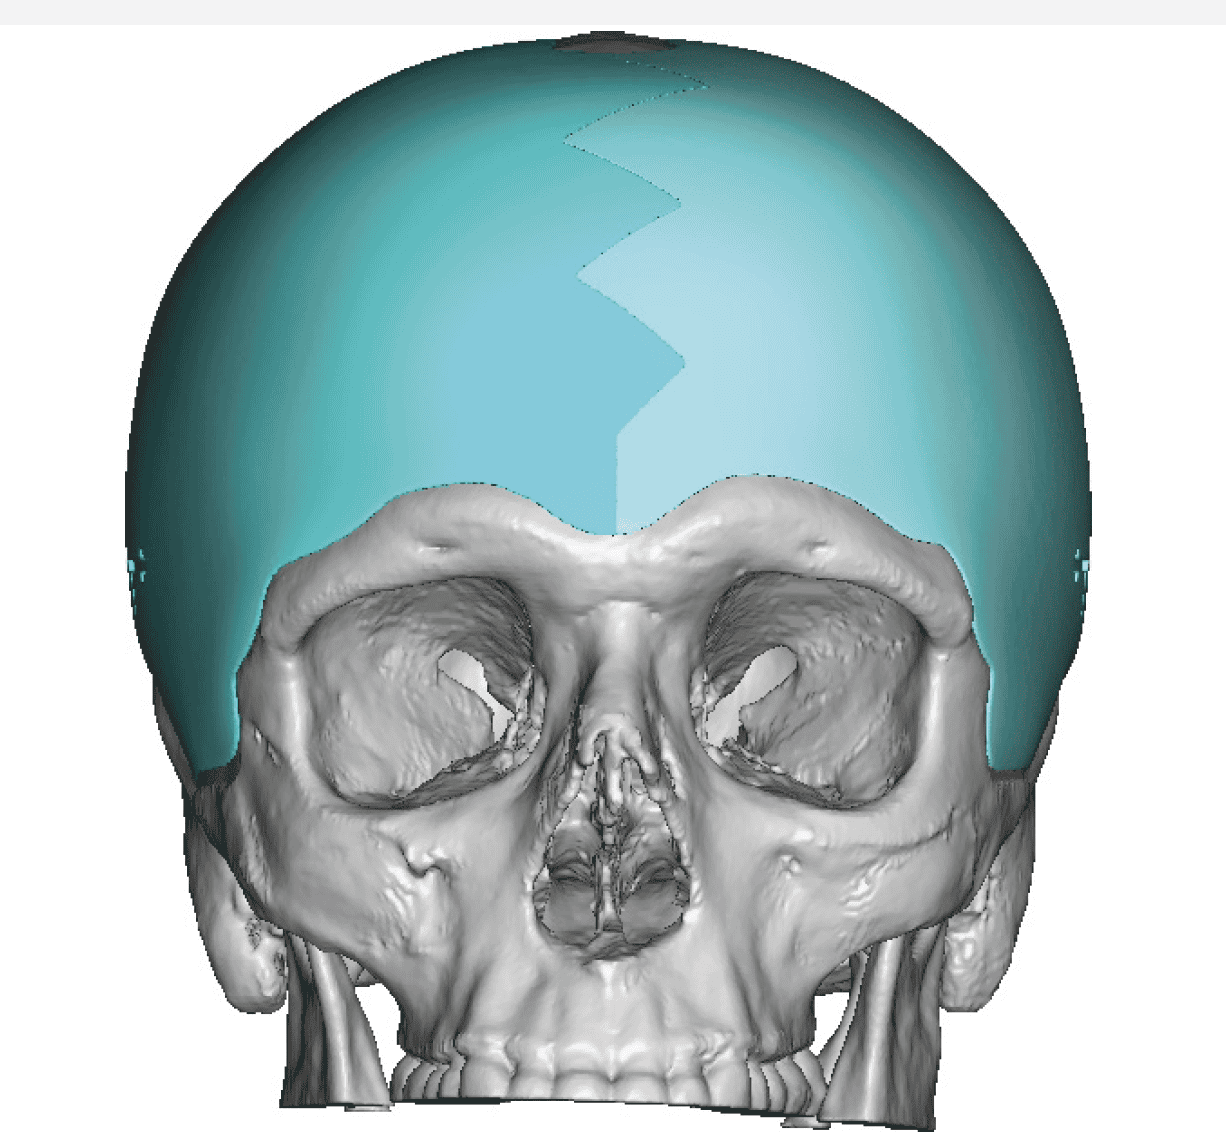

Patient 51

Desire for improved head shape that has a less peaked shape.

Placement of custom skull implant.

Desire for improved head shape that has a less peaked shape.

Placement of custom skull implant.